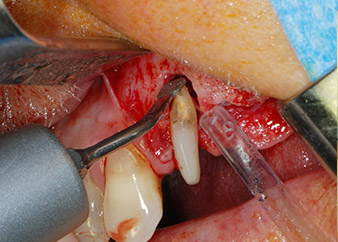

Въпреки това, ние се придържахме към първоначалния си план да запазим и двата зъба като абатмънти за временен мост по време на 6-месечната остеоинтеграция на имплантите. При повторна интервенция, ситуацията трябва да се преразгледа. Първо, в опит да се овладее ендо-перио проблема, останалата повърхност на зъба е внимателно обработена с пиезохирургично оборудване (Piezomed, W&H, използван с накрайник S1 под формата на шпатула, първоначално проектиран за ерозия на латералната синусна стена) (Фиг. 4).

След това апексът се изпилява със същия инструмент, за да се отстрани остатъчната инфектирана апикална тъкан и да се намали възможното допълнително усложнение по кореновите канали (апикоектомия) (Фиг. 5). Ретроградно запълване не е необходимо, защото ортоградното запълване току-що е ревизиран.

Фиг. 4: За да се съхрани зъбът като временен абатмънт, периодонциумът е изпилен с пиезохирургично оборудване...

букален апекс на зъб 24

Фиг 5: ... и букалният апекс на зъб 24 е обработен със същия инструмент (апикоектомия).